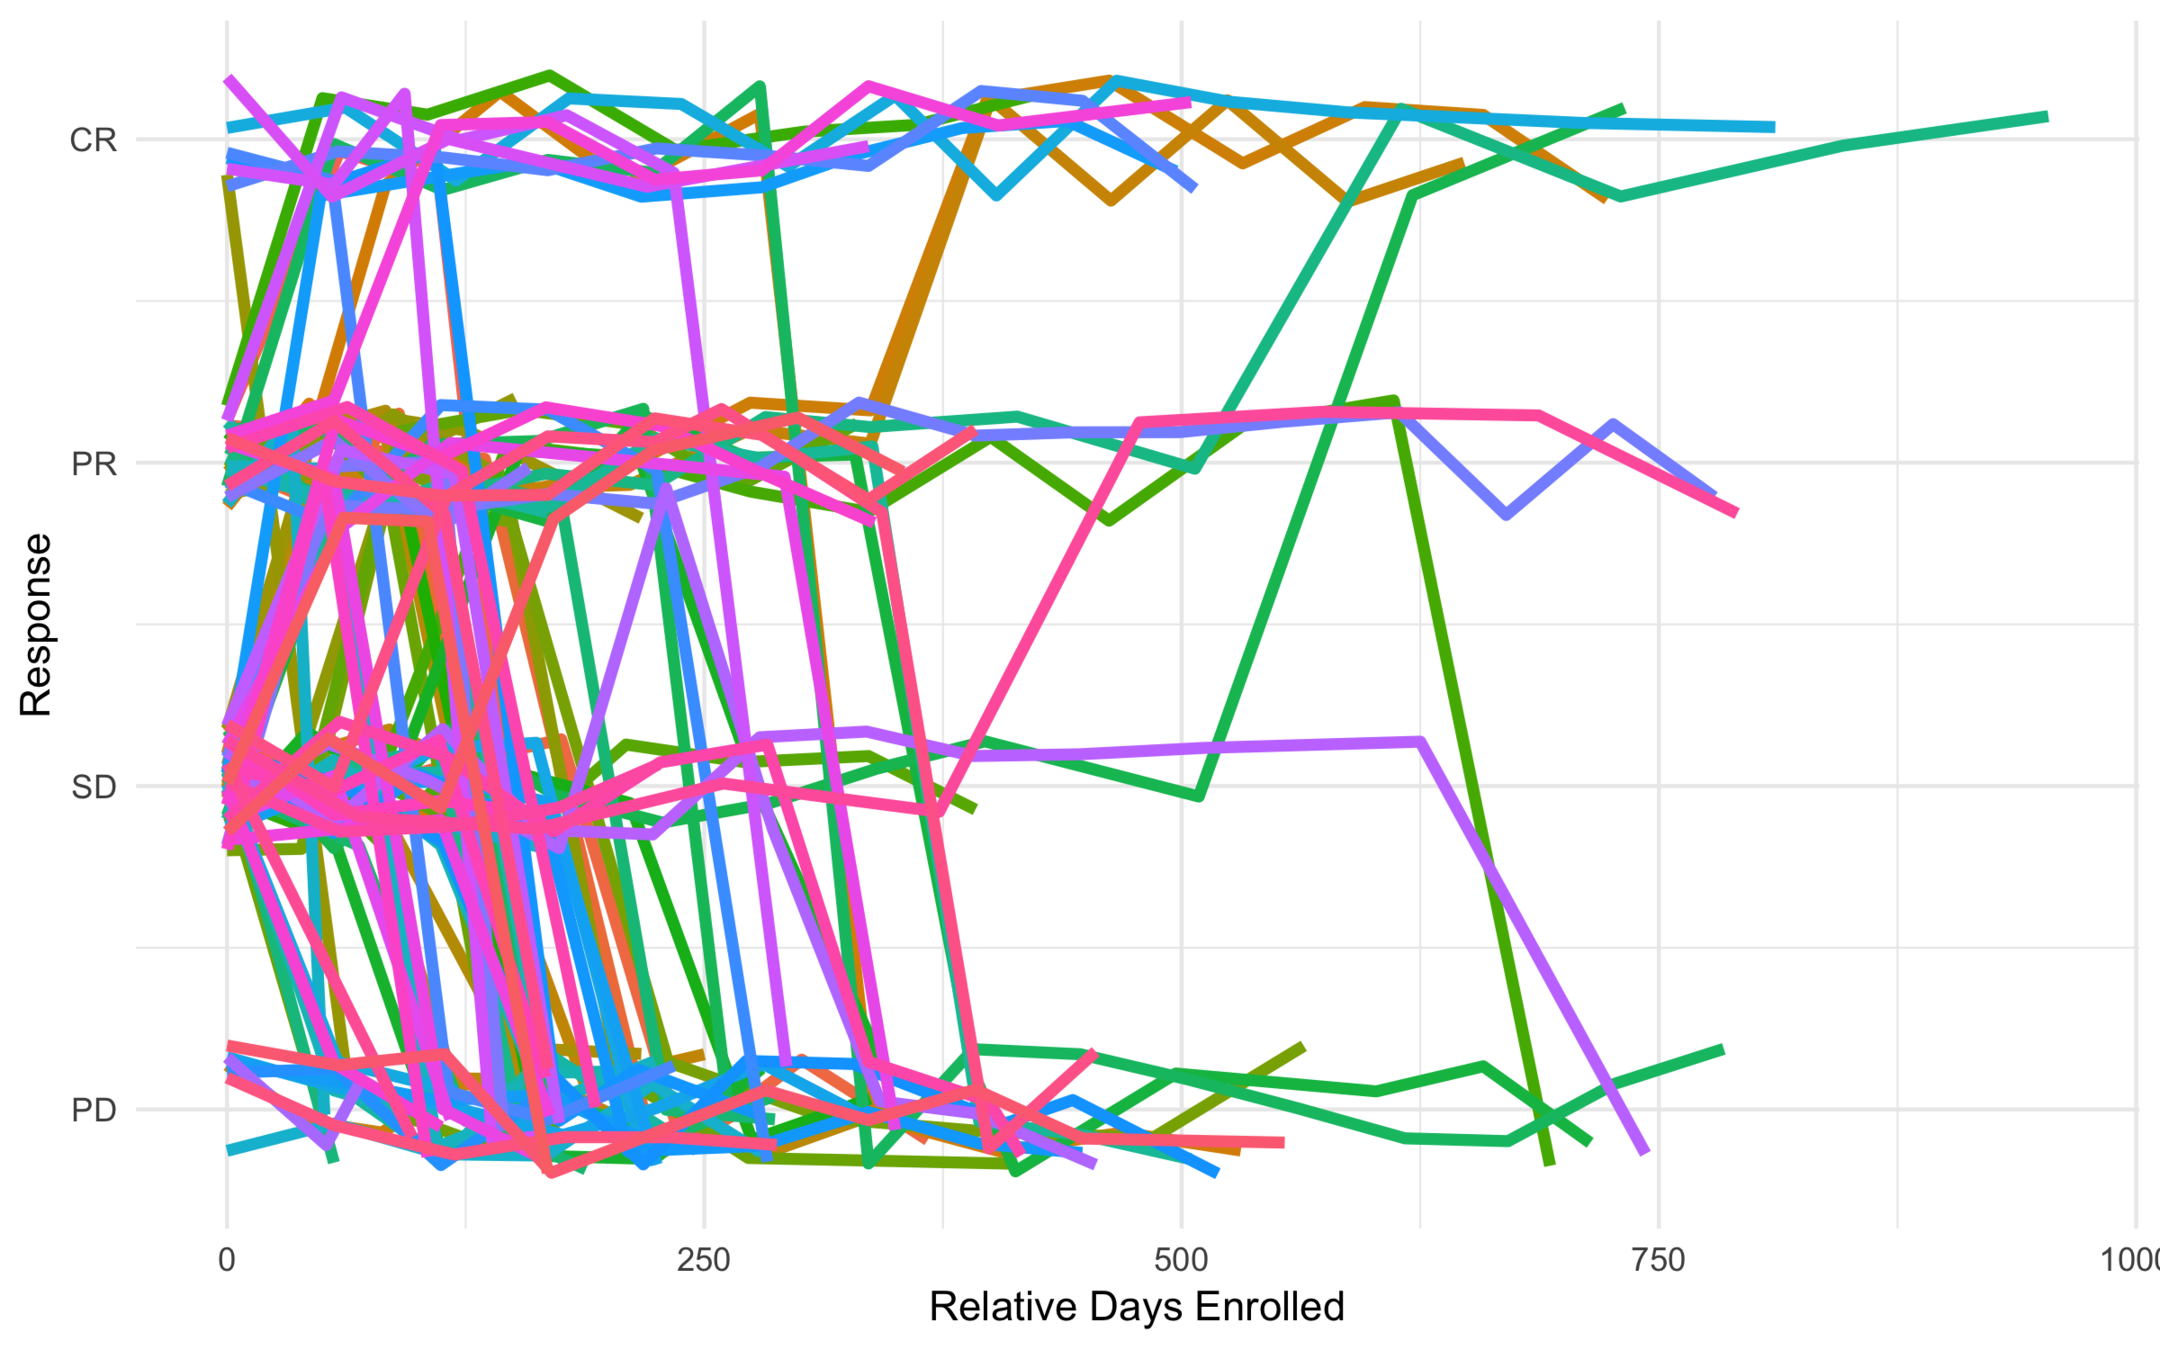

All Trajectories

Low Risk

Intermediate Risk

High Risk